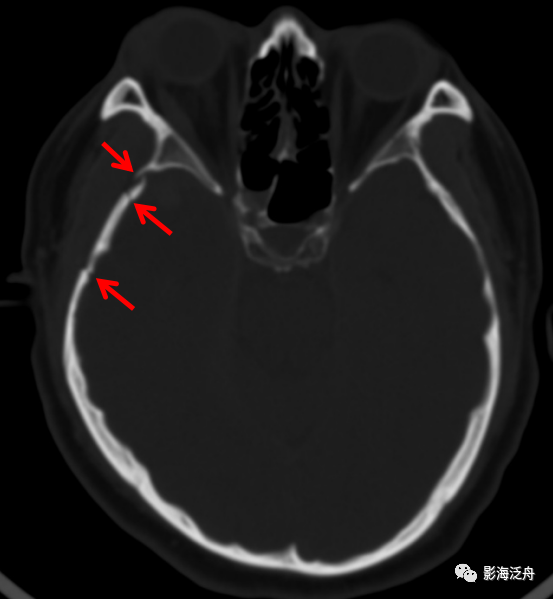

骨窗位见右颞骨近乳突处骨折,左颞骨折!

右侧颧弓骨折(红箭),注意对照前文的解剖标注图里的标注区2,颞骨与

右侧颧弓粉碎性骨折(红箭头),右侧下颌窝周围颞骨多发线性骨折(绿箭).